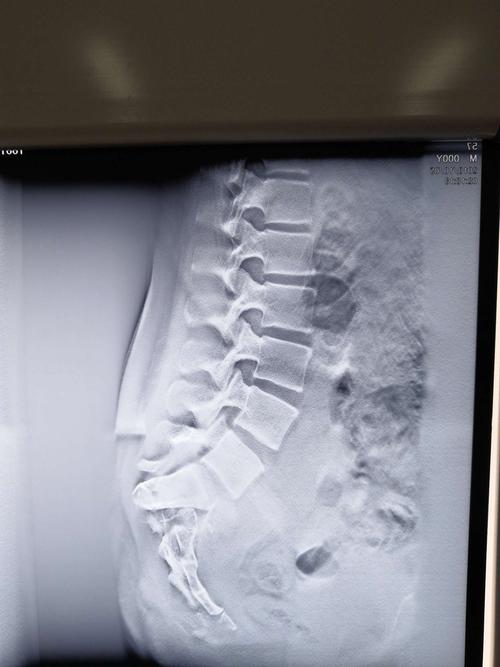

左侧骶骨翼骨折图片

左侧骶骨翼骨折图片,右侧骶骨翼骨折图片

华亭市二院成功开展骨盆骨折伴骶骨骨折手术一例

骶骨的形状有些勉强,是否以往有过骨折所致的畸形?

术前骶骨骨折

骶骨骨折图片

骶骨骨折影像图片

骶尾骨骨折x线图片

骶骨骨折x片